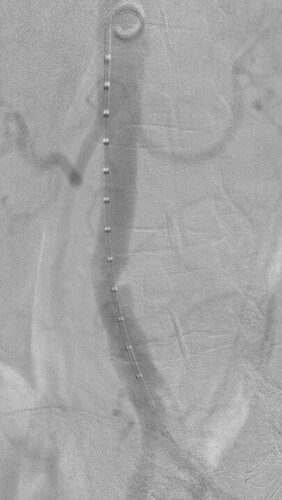

Nice image! You show the vessel in the simulated fluoro image as a surface rendering now. You can try to use the “Virtual contrast filling” section to make the appearance more realistic (the module fills the CT image uniformly inside the segment/model with the density you specify).

Yep, that purpose was what I did not understand yet.

Virtual contrast filling can be useful to simulate stronger contrast filling (e.g., you have a CT with IV contrast injection and you want to simulate local contrast injection) or you want to add anything to the CT that was originally not there (e.g., a stent or device).

Here is the procedural image with the C-arm oriented as simulated. I find it a faithful reproduction for a first try, and remain confident for subsequent ones.

Here it means less radio emission and less contrast medium injection.

This module should be viewed as a wonderful add-on to anyone working with a C-arm, beyond the cardio-vascular realm, orthopedists for example.